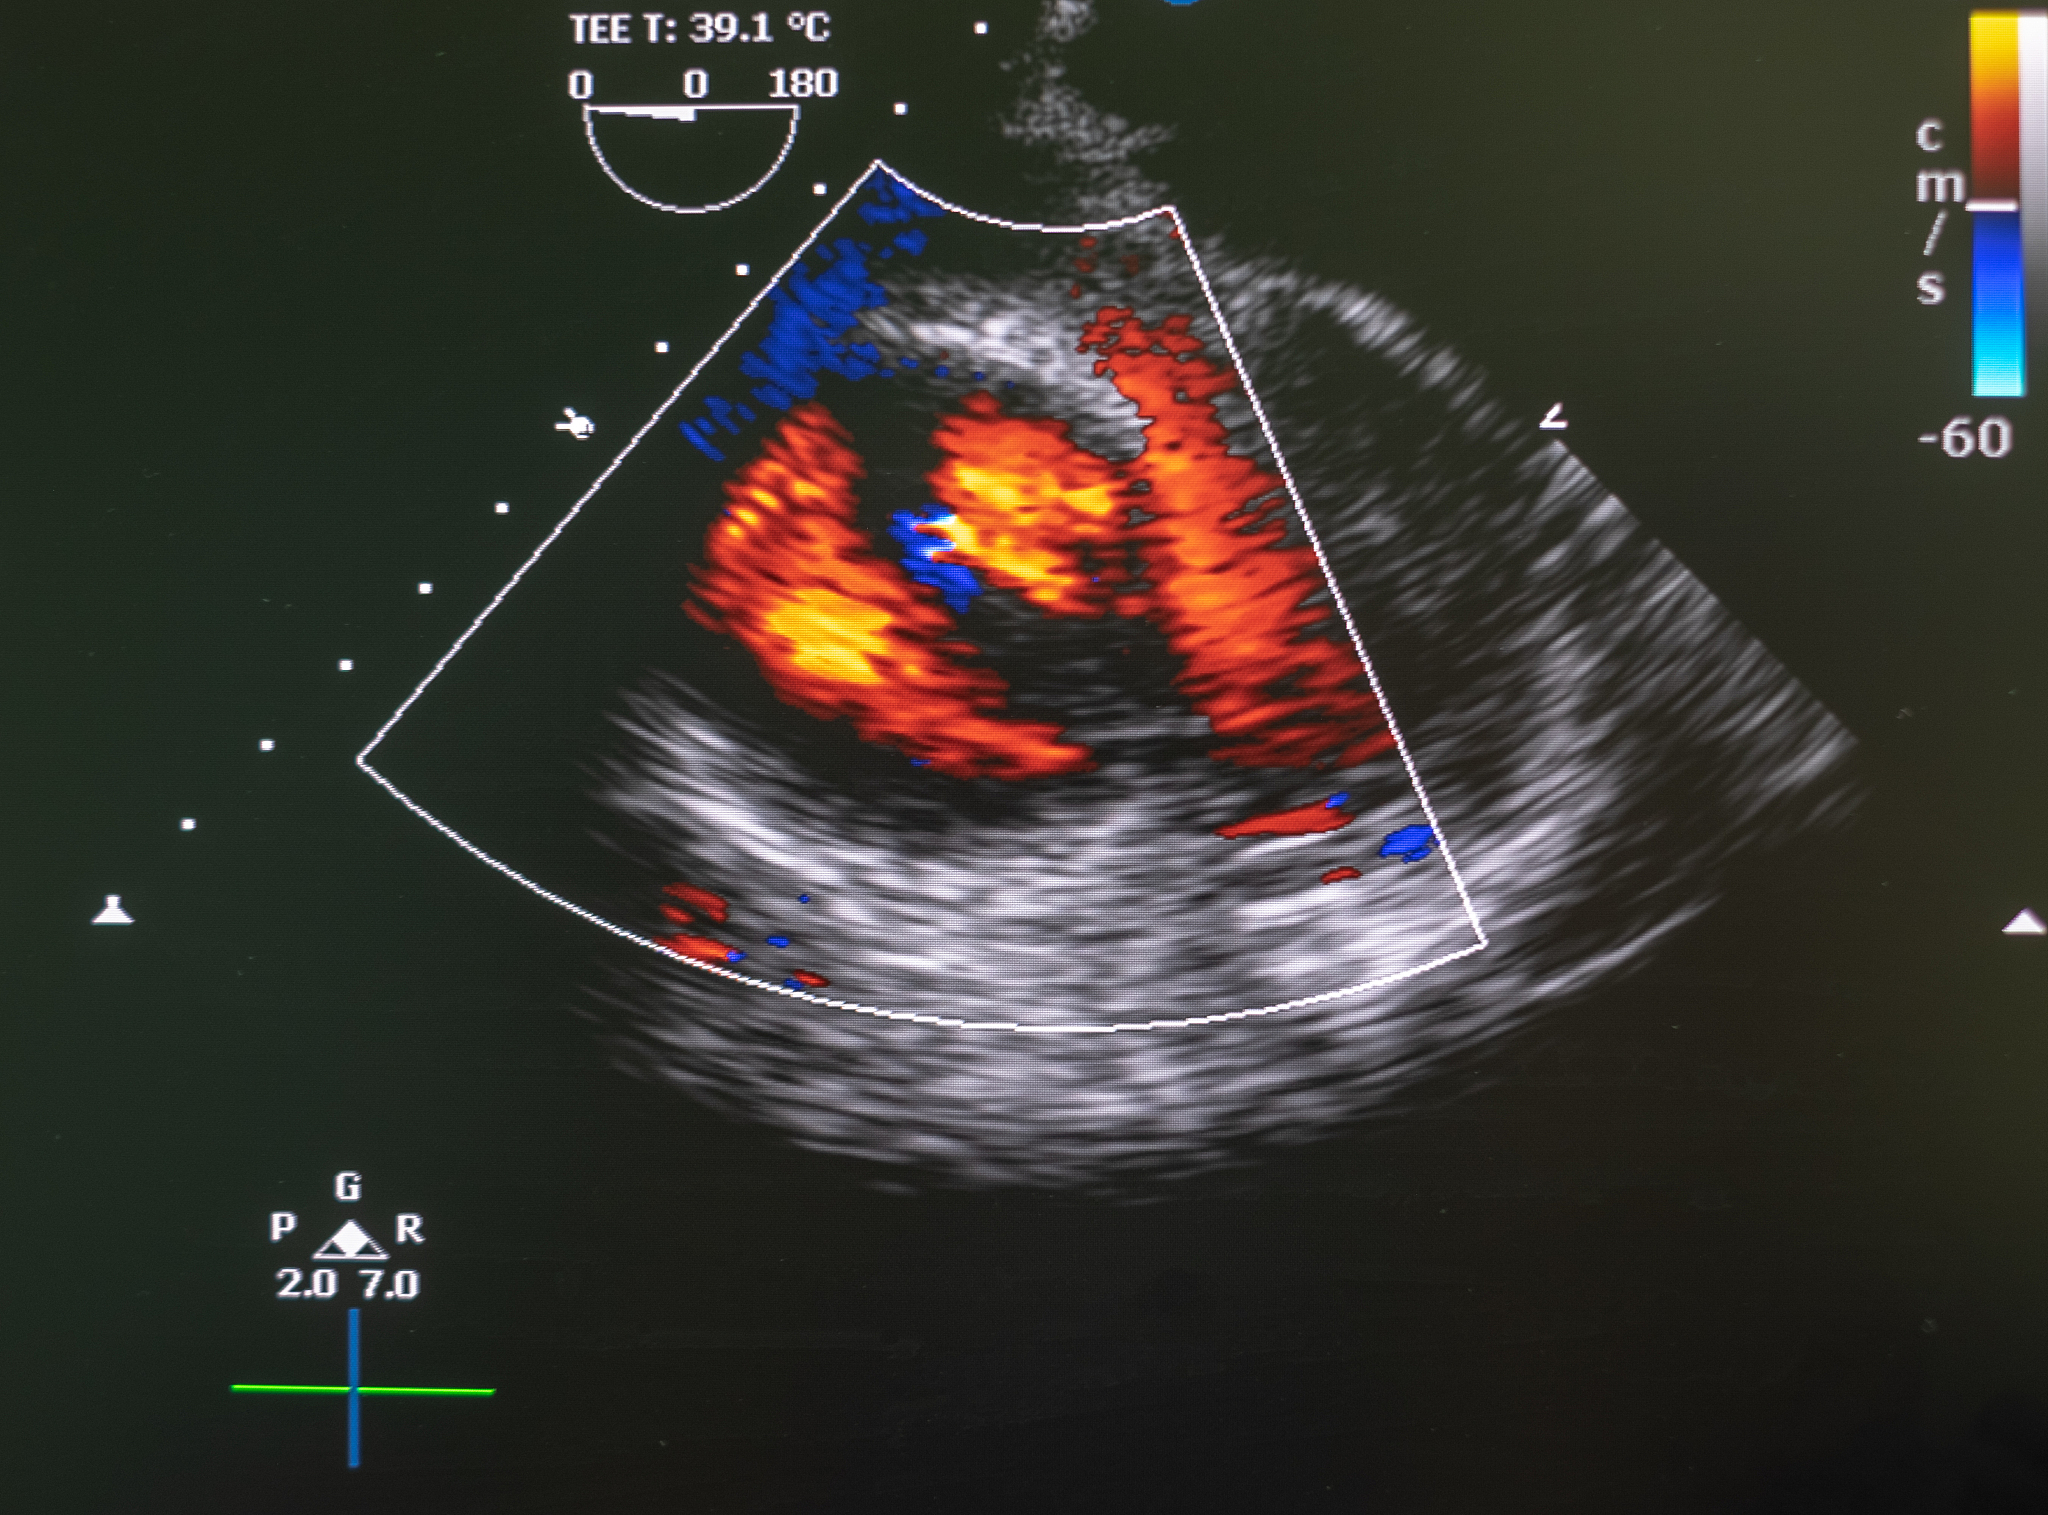

Application of intracavitary ultrasound contrast imaging in the bile duct.

腔内超声造影是近年来发展起来的一种新型超声诊断技术,通过注入微泡造影剂,增强超声信号,提高图像质量,从而提高胆管疾病的诊断准确性。该技术已广泛应用于临床,为临床医生提供了更清晰的图像信息,帮助他们更准确地诊断和治疗胆管疾病。

腔内超声造影在胆管疾病的诊断和治疗中具有重要的应用价值,为患者提供更安全、更有效、更精准的医疗服务。

胆管腔内超声造影应用:提高诊断准确性